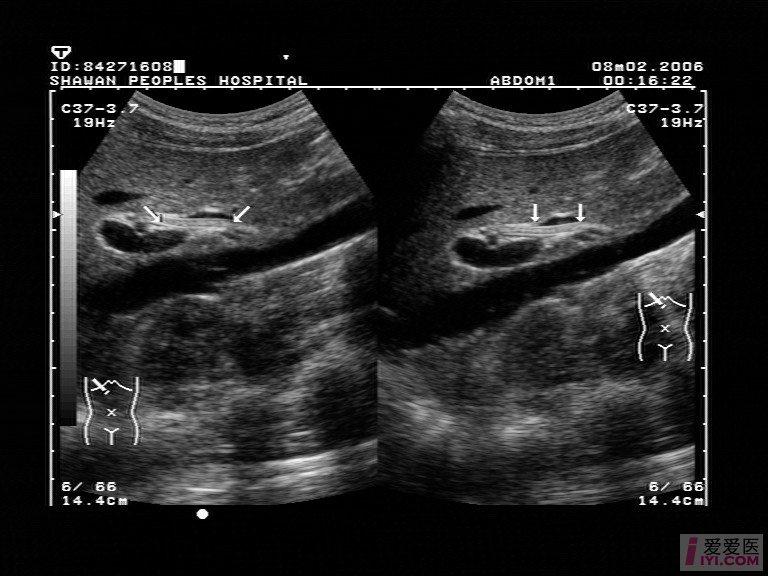

【讨论】【贴图】胆道蛔虫?

图片尺寸768x576

19:15胆总管蛔虫声像图——zengerya 胆道蛔虫病是常见的急腹症忠换

图片尺寸762x537